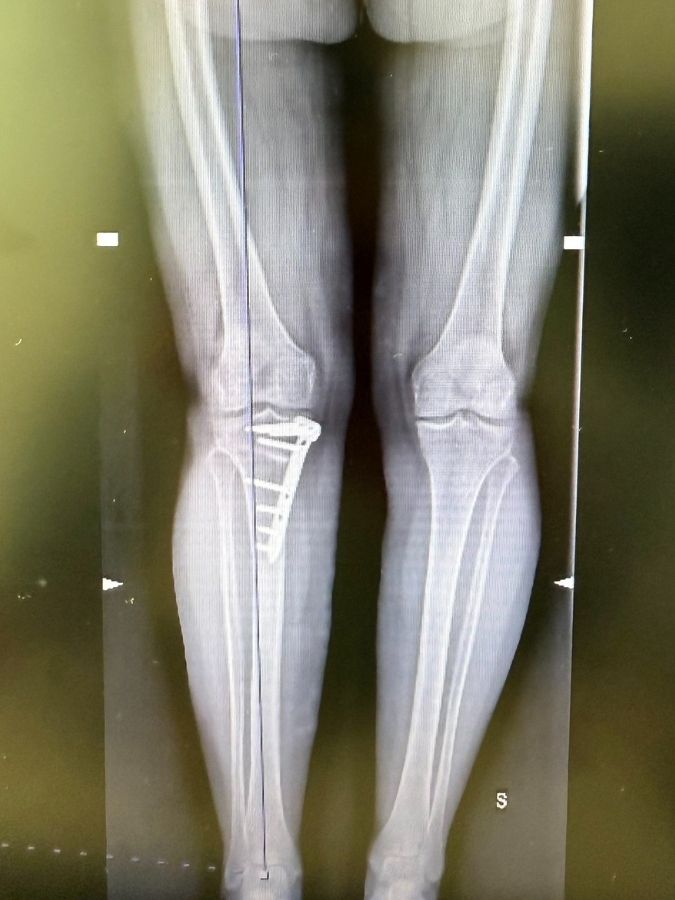

Per quanto riguarda la tecnica chirurgica, da anni sono propositore in Italia di:

1-la tecnica biplanare, che prevede un taglio osseo a V, con numerosi vantaggi rispetto all’osteotomia classica monoplanare (in cui il taglio osseo viene effettuato in un’unica direzione):maggiore stabilità e migliore e più rapida guarigione

2-le placche ad angolo stabile ovvero con viti che si “incastrano” nella placca, permettendo di caricare subito l’arto operato ed avere nel contempo grande stabilità dell “frattura” che noi creiamo (la cosiddetta osteo-tomia = taglio dell’osso)